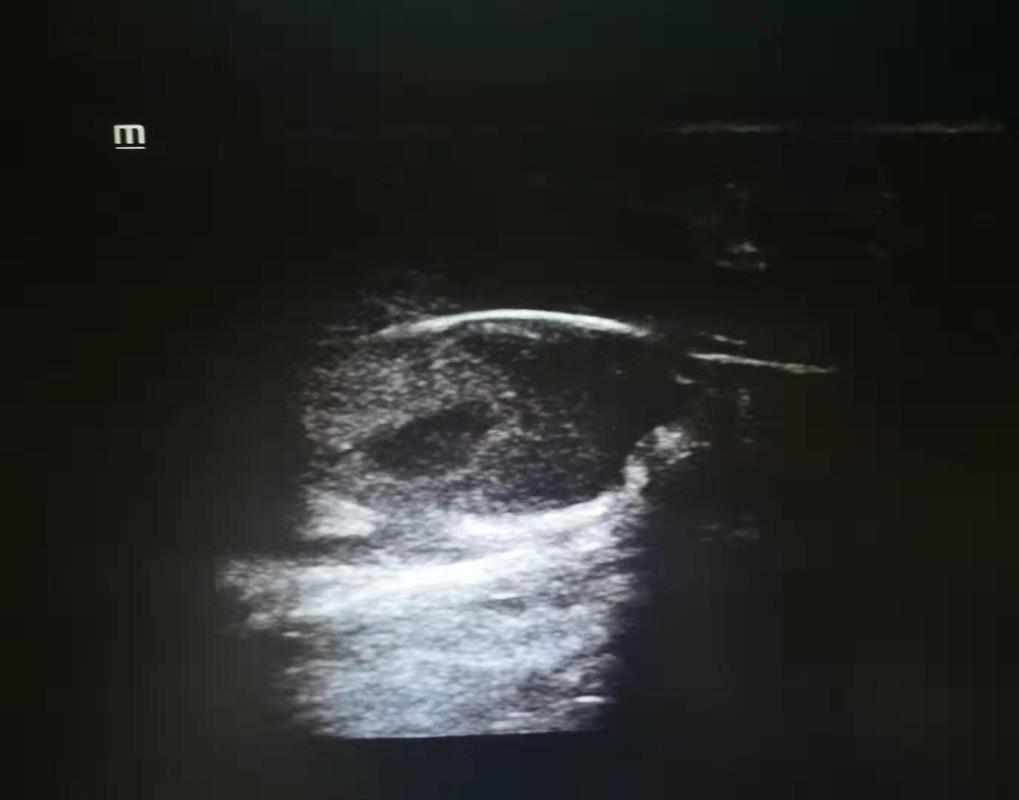

医生接诊后详细询问了李先生的情况,观察患处后,医生初步判断李先生并非单纯的化脓感染性包块。建议其进行了超声检查。超声科医生一查,竟发现脓包中有一条粗线一样的强回声影像。医生判断李先生可能是患上了一种少见的疾病——藏毛窦,并且发生了化脓感染。果然,手术中医生切开了脓包,从中取出一缕一指长的毛发。